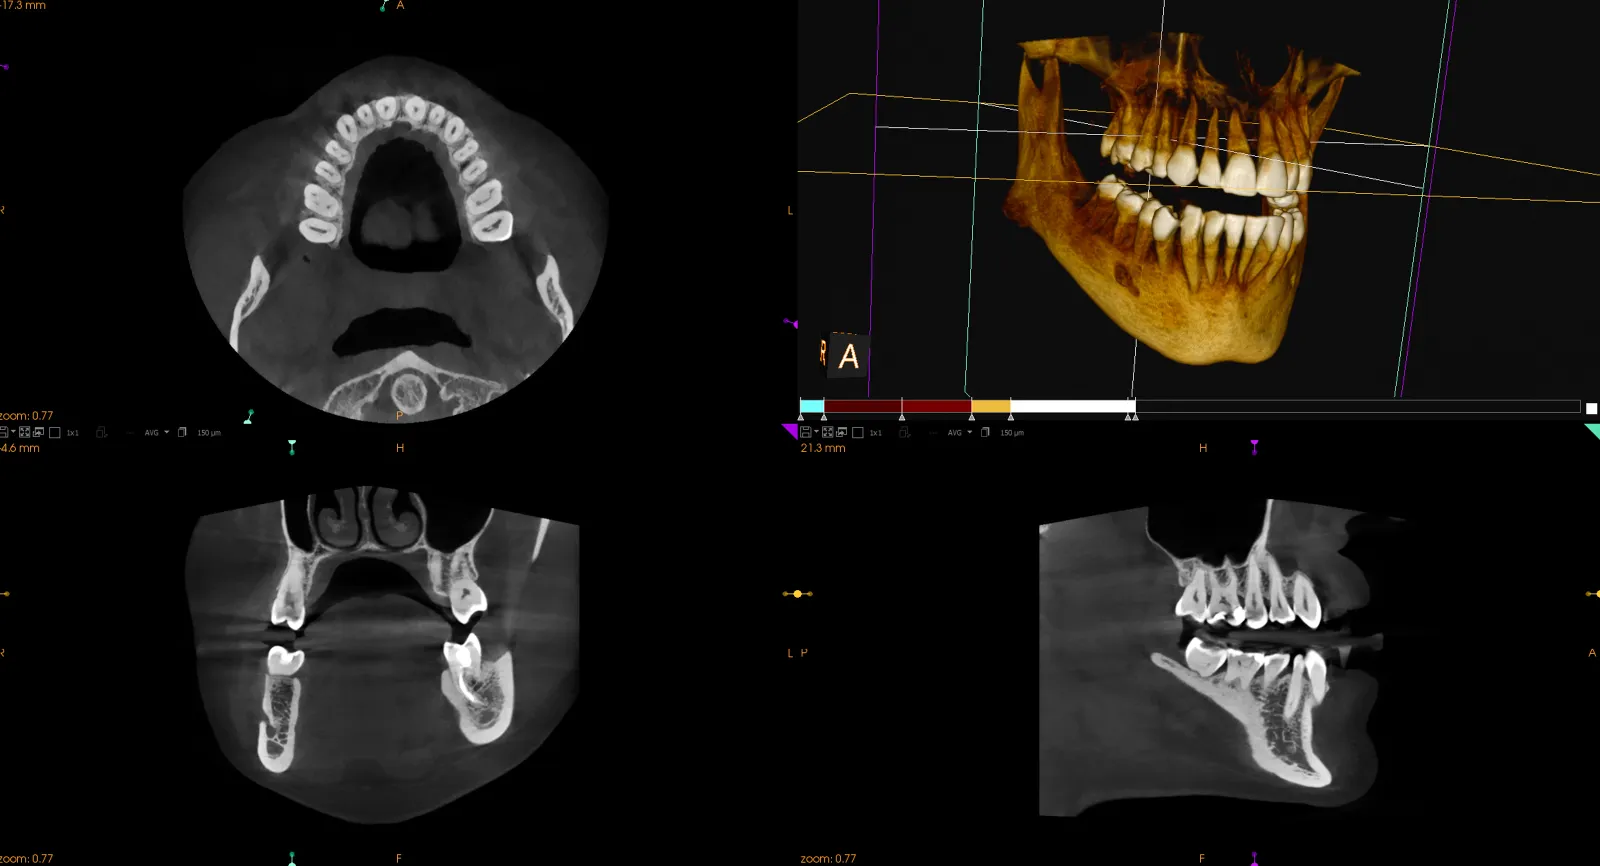

Tomografia stomatologiczna, funkcjonująca także pod skrótową nazwą TK, to rodzaj badania radiologicznego w ujęciu 3D, wykorzystującego promienie rentgenowskie do obrazowania tkanek w 3 płaszczyznach: czołowej, strzałkowej (bocznej) i horyzontalnej. Jest uznawana za najszybszą i całkowicie bezinwazyjną metodę diagnostyki. Po tomografię stomatologiczną sięgają stomatolodzy, implantolodzy, a także specjaliści w dziedzinie chirurgii stomatologicznej, ortodoncji i endodoncji. Lekarz, który wykonuje tomografię stomatologiczną, otrzymuje widok wszystkich struktur twarzoczaszki – rzeczywisty, trójwymiarowy obraz tkanek miękkich, zatok szczękowych oraz zębów. Obraz z lampy prześwietlającej wysyłany jest na monitor komputera. Jest on niezbędny, by wykryć wszelkie nieprawidłowości i stany zapalne oraz opracować leczenie pacjenta. Widok z tomografu pomoże zaplanować np. kąt wprowadzenia implantu zębowego, ocenić drożność zatok szczękowych lub ustalić gęstość tkanki kostnej.

Tomografia komputerowa zębów ma szerokie zastosowanie diagnostyczne – jest pomocna, by ocenić ilość i jakość kości oraz stan i położenie zębów. To badanie diagnostyczne jest szeroko stosowane m.in. w chirurgii stomatologicznej i implantologii, w tym do zaplanowania miejsca na implanty. Tomografia komputerowa zębów jest również pomocna w ortodoncji, bo pomaga rozpoznać i zdiagnozować wszelkie nieprawidłowości w obrębie jamy ustnej. Ponadto stosuje się ją w stomatologii zachowawczej i endodoncji, a także protetyce – na etapie przedprotetycznym i we właściwym leczeniu protetycznym.